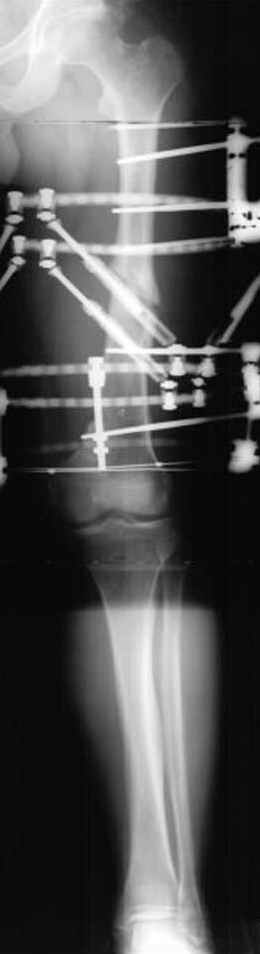

Отправитель: Djoldas Kuldjanov 23 Ноябрь 2004, 18:21

пластическая модель; и коррекция бедра аппаратом Илизарова.

Узкий к-м канал - тонкий гвоздь- усталостный перелом дистальных винтов - развитие нестабильности и как ее результат остеолиз вокруг гвоздя - деформация анатомической оси бедра. Похоже, что я понял почему аппарат, а не новый гвоздь:-)

ЕТ - Изначально костно-мозговой канал бедра был узкий, дальнейшее его рассверливание ещё больше скомпрометирует прочность бедра( латеральный кортекс дистального отломка уже истончен), приведет к дефекту наружной стенки - хотя это только мои догадки - хотелось бы знать мнение Джолдаса о выбранной тактике.